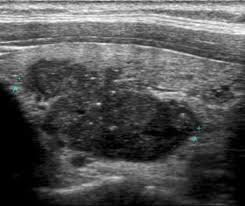

В серошкальном режиме визуализируется гипоэхогенный узел неправильной формы с неровными и нечёткими краями, расположенный в пределах одной из долей или в перешейке.

В режиме мягкотканевого сканирования определяется микрокальциноз в виде множественных точечных гиперэхогенных включений без акустической тени, характерный для папиллярного варианта.

Фиксируется вертикальное расположение узла с соотношением передне-заднего и поперечного размеров больше единицы.

Контуры узла могут быть инвазированы в капсулу железы или выходить за её пределы с нарушением эхогенности окружающих тканей.

В допплеровском режиме выявляется выраженная внутренняя и периферическая васкуляризация с хаотичным распределением сосудистого рисунка.